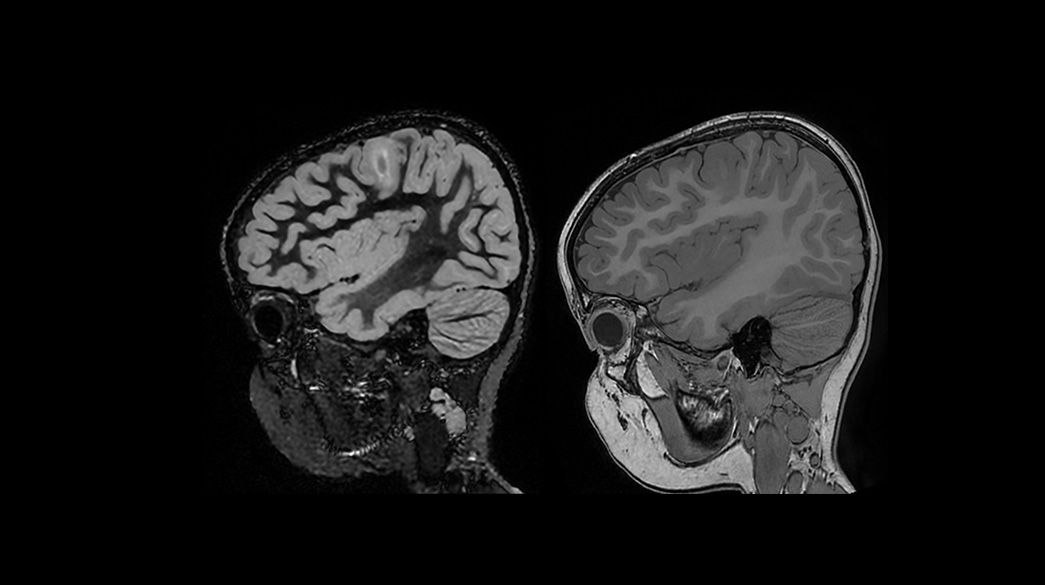

Pediatric MRI imaging applications

Diagnostic confidence and consistency